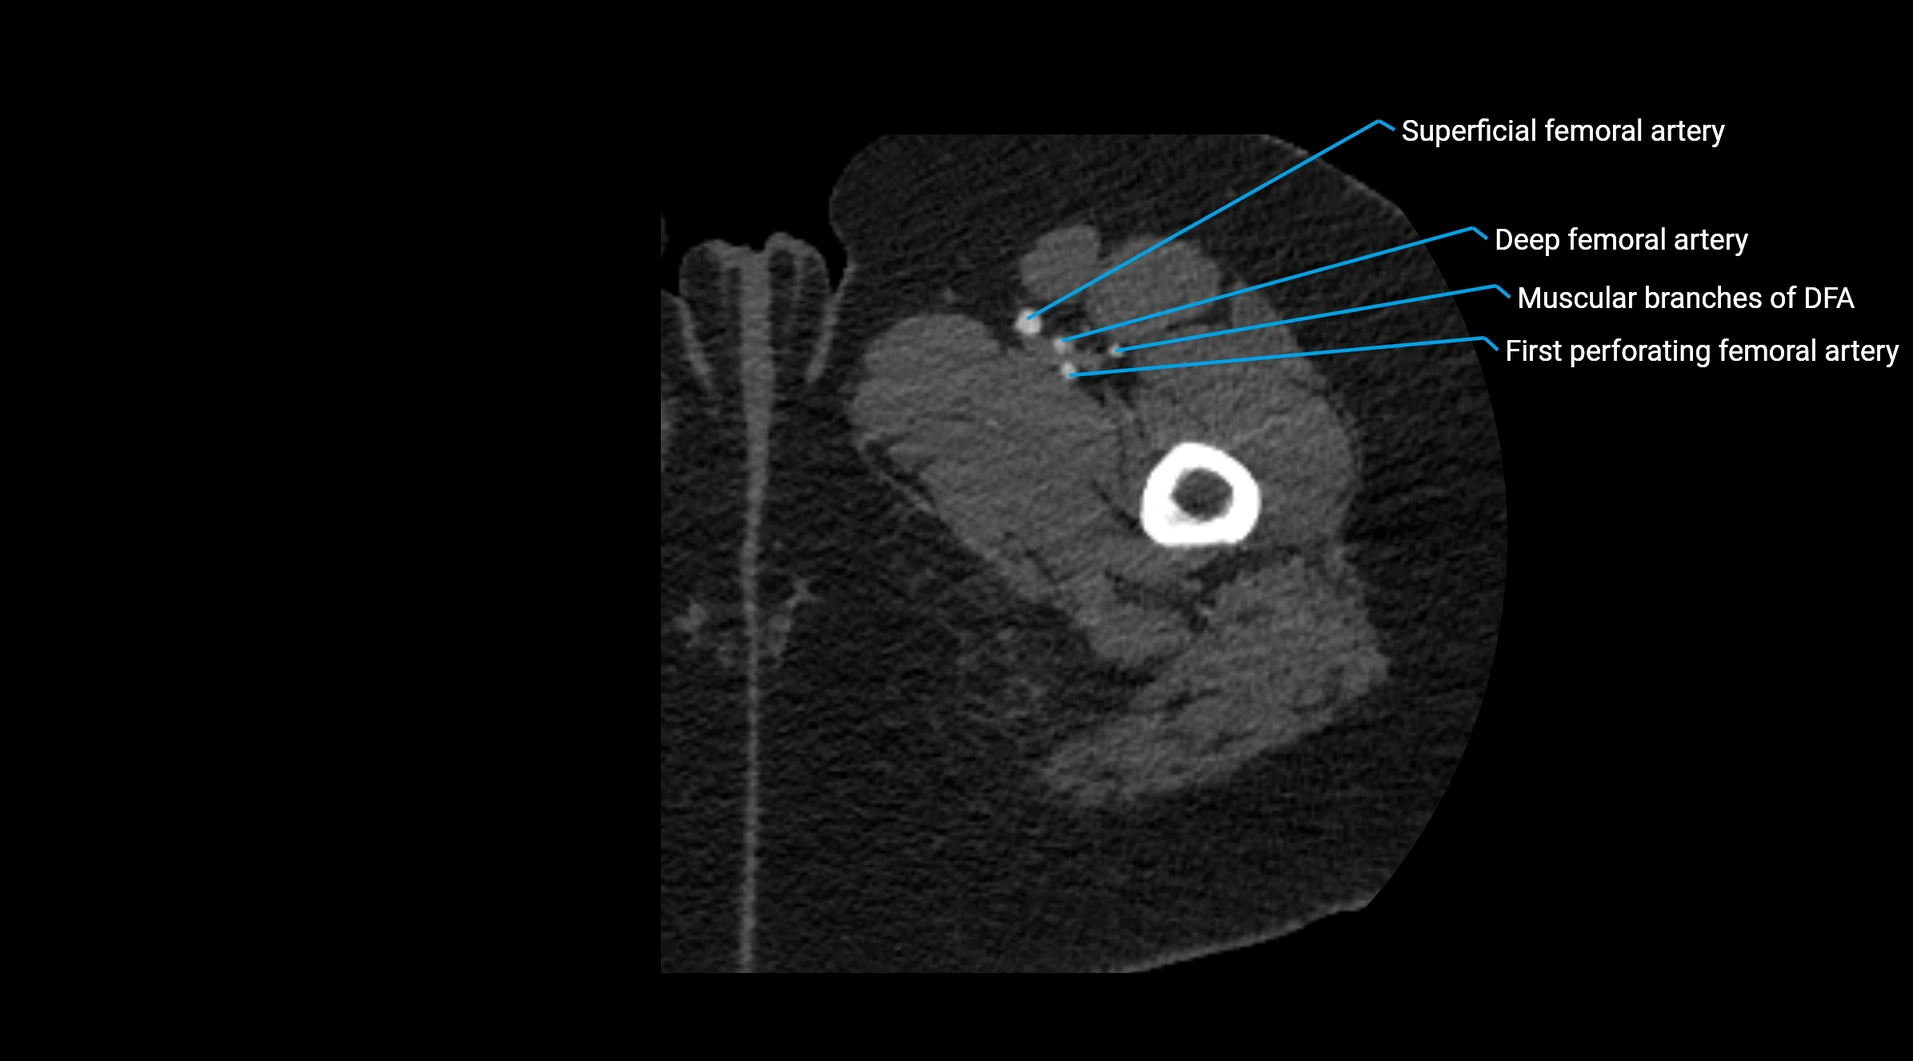

CT images

image